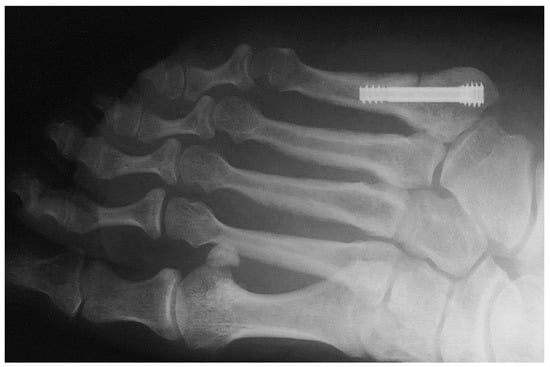

Figure 1 shows an X-ray snapshot of the fixation of a fifth metatarsal fracture with a headless screw. Metatarsal fractures are the most common fractures of the leg, the most common among them being the fifth metatarsal fracture. Metatarsal fractures are mostly caused by direct impact (car accident, fall, etc.) or during sports (typical injuries of football players, etc.). There are multiple types of metatarsal fractures, such as the Jones fractures, proximal diaphyseal, or fatigue fractures. Interested readers may find more information in [5,6].

Figure 1. Application of a headless screw to the fifth metatarsal bone.